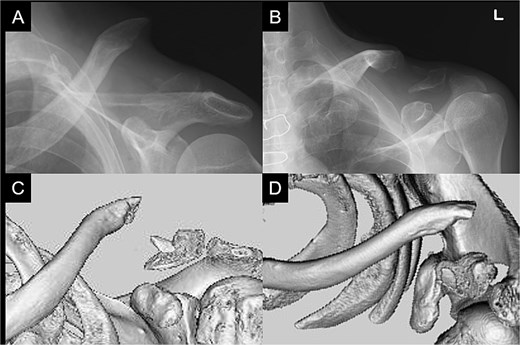

Postoperatively, the left arm of the patient was immobilized in a sling for 3 weeks. The pain gradually subsided, and the patient resumed heavy work without pain at 6 months postoperatively. At 1 year postoperatively, the patient had a constant score of 98. Bone union was confirmed (Fig. 4A–D).

Radiographs (A and B) and CT scans (C and D) captured at 1 year postoperatively show union of the bone.